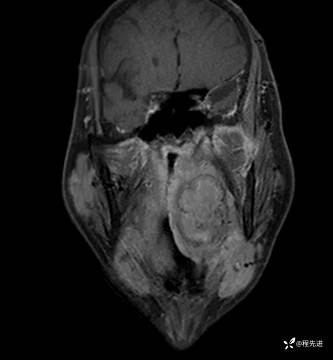

MRI平扫+增强:

T2压脂:

T1:

T1增强: